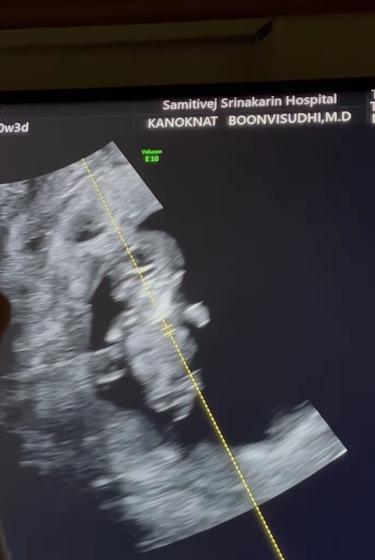

โดยสาว ตุ๊กตา ได้ระบุแคปชั่นว่า "วัยรุ่น สองขีด ที่ไม่ได้แปลว่าเป็นโควิทจ้าาาาา อ่ะ กระหน่ำตั้งชื่อกันมาเลยจ้าาาา #ตุ๊กเบลไม่ได้เป็นแฟนละนะ #ตุ๊กเบลกำลังจะมีลูกละนะ" โพสต์ต่อมา เป็นภาพคู่สามีพร้อมใบอัลตราซาวนด์ลูกน้องในครรภ์พร้อมระบุแคปชั่นว่า "Being family #threeofus #พ่อโปรเบล #แม่โปรตุ๊ก"

ล่าสุดว่าที่คุณแม่ ตุ๊กตา ได้อัปเดตหลังจากที่ไปตรวจร่างกายกับคุณหมอ โดยระบุว่า "11 weeks pregnant check-up วันนี้มาตรวจร่างกายหนูค่า จริงๆ เราเจอกันครั้งนึงแล้ว ตอนวันเกิดคุณพ่อ ตอนนั้นอยู่ดีๆหนูก็เลือดออก (นี่คือสาเหตุที่ยังไม่บอกใครตอนนั้น) แม่ตกใจมาก เจอกันครั้งนั้น หนูอยากให้พ่อเห็นว่าหนูมีหัวใจแล้ว แต่หนูไม่ได้เป็นอะไรมาก แค่แม่เดินเยอะ เดินแรงไปนิดนึง แม่ลืมไปว่าแม่แก่แล้ว ตอนนั้นหนูยัง 5 มิลอยู่เลย

มาหาคุณหมอกนกนาถครั้งนี้ หนู3เซนแล้วว เปิดไปเจอตอนแรกคุณหมอบอกหนูหลับอยู่ หลับปุ๋ยเลย หนูหลับตอนเที่ยง แต่ทุกคนน่าจะเสียงดังมาก โดยเฉพาะ อาม่ากับคุณพ่อ หนูก็เลยตื่นเลย หนูดิ้นดุ๊กดิ๊กน่ารักมากก คุณพ่อตื่นเต้นมาก จากหนูเป็นก้อนกลมๆ วันนี้หนูมาเป็นคนเลย มีนิ้ว มีทุกอย่างครบแล้ว คุณพ่อตกใจ 555 คุณพ่อคุณแม่ดีใจมากที่ได้เจอหนู แต่หนูซนน้อยๆหน่อยนะลูก แม่อ้วกทั้งวันเลยลูกเอ้ย รักหนู จากพ่อกับแม่ #ตุ๊กเบลได้เป็นพ่อแม่ละนะ".